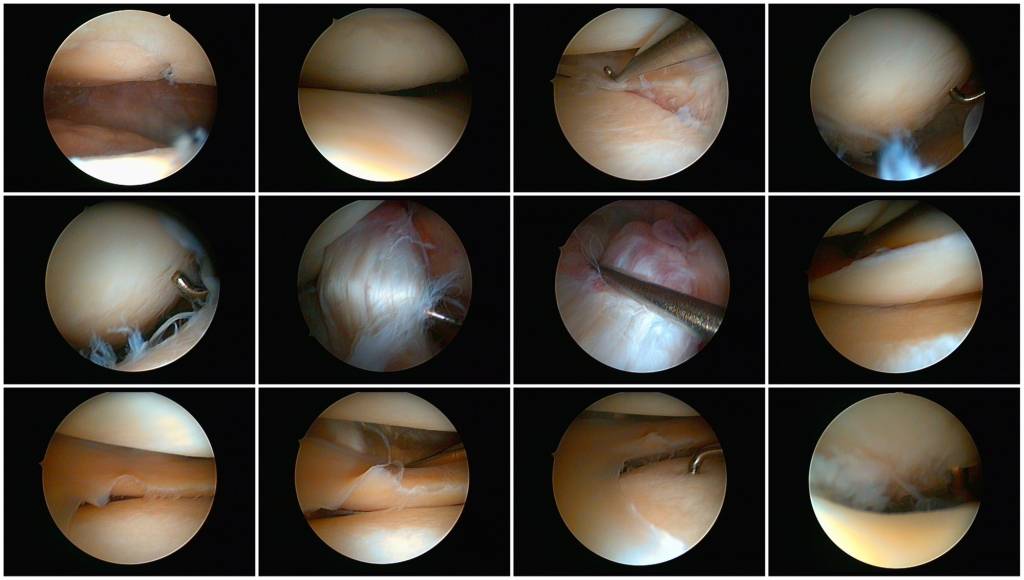

Nach einer Befragung des Patienten (Anamnese) erfolgt eine gründliche körperliche Untersuchung. Dabei kommen verschiedene Handgriffe und Untersuchungstechniken zum Einsatz. In bildgebenden Verfahren, z. B. Röntgen, Ultraschall, Computertomographie (CT) oder Magnetresonanztomographie (MRT), können Veränderungen erkannt werden. Wichtig ist in bestimmten Fällen (z. B. beim Verdacht auf Rheumatoide Arthritis) eine Blutuntersuchung. In einer Gelenkspiegelung (Arthroskopie) können krankhafte Veränderungen über ein optisches Gerät gesehen und beurteilt werden.

Falls nichtoperative Behandlungsmethoden oder alternative Operationen nicht möglich oder erfolgreich sind, so kann der Einsatz eines künstlichen Kniegelenks (Prothese, Endoprothese) vorgenommen werden. Andere Operationsmöglichkeiten beinhalten z. B. eine Umstellungsoperation (Achskorrektur bei Fehlstellung) oder eine therapeutische Gelenkspiegelung (Arthroskopie).